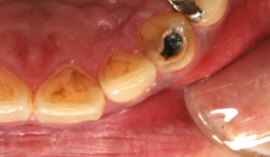

むし歯を取り除いたところ

コンポジットレジンをつめて、むし歯の処置が終了したところ

コンポジットレジンをつめて、

むし歯の処置が終了したところ